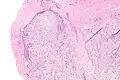

Micrograph of nodular fasciitis showing the haphazard arrangement of cells (tissue culture-like pattern). H&E stain.

The microscopic histopathology of hematoxylin and eosin stained nodular fasciitis tumors consists of spindle-shaped myofibroblastic cells.[8] These cells are in a myxoid or a collagenous (high content of collagen fibers) tissue background. The neoplastic myofibroblasts are arranged in whorls and/or short bundles. These cells may show high rates of replicating as judged by their mitotic index, but these mitoses are normal in appearance. The tumor tissues often contain red blood cells, lymphocytes, and giant osteoclast-like cells, and may contain sites of bone-like tissue.[10] NF is sometimes classified into three subtypes based on its predominant histopathological pattern: myxoid or reactive (type I), cellular (type II), and fibrous (type III).[4] These patterns appear related to the duration of the lesion, with the myxoid variant tending to have the shortest duration and the cellular and fibrous variants tending to have progressively longer durations.[14] Immunohistochemical analyses indicate that the cells in NF usually express smooth muscle actin, muscle specific actin, and vimentin proteins but generally do not express CD34, S-100 protein, desmin, trypsin, factor VIII, F4/80, or HLA-DR1 proteins.[10] Uncommonly, the cells in NF tumors express the CD68 (a histiocyte-specific marker) protein.[4]